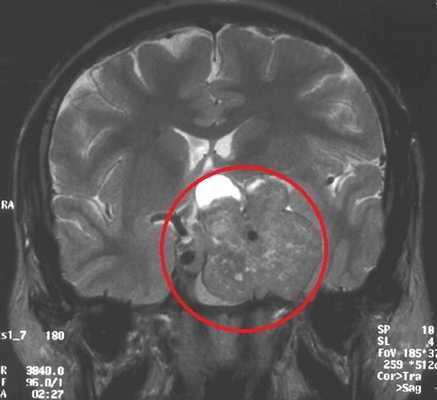

МРТ гипофиза. На МР-томограмме определяется гигантское образование неоднородной структуры (обведено) — макроаденома гипофиза.